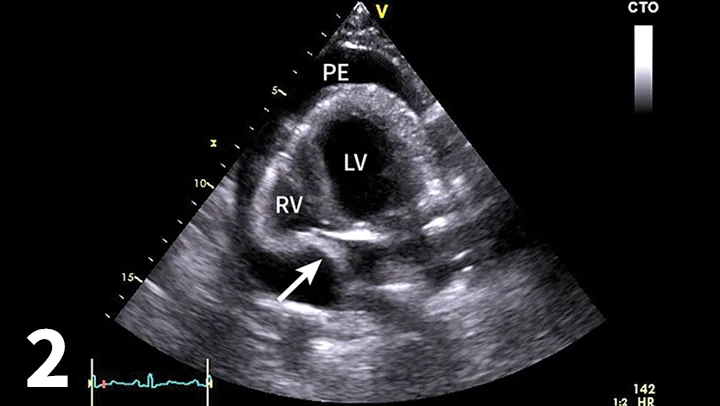

• Echocardiography confirms an echo-free space between the heart and the pericardium (Figure 1), may show cardiac tamponade (Figure 2), and may detect mass lesions.

Short-axis (hammerhead) view showing the left ventricle (LV), interventricular septum (IVS), and right ventricle (RV) surrounded by pericardial effusion (PE), which can be seen within the bright pericardium (asterisk). A short-axis view of the heart allows visualization of pericardial effusion by identifying an anechoic ring of fluid within the bright pericardium, helping differentiate the fluid from pleural effusion. Image courtesy of Meriel LeSueur, DVM

• Echocardiography